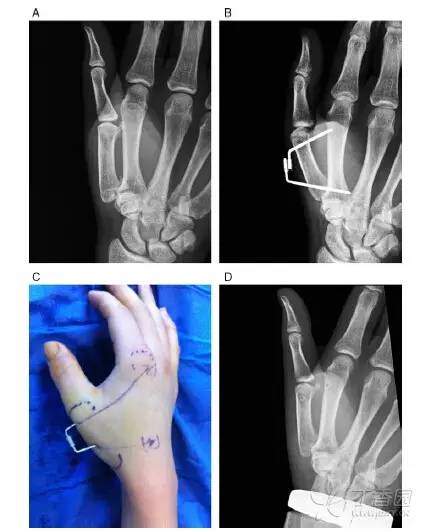

图 2. 案例 2,17 岁女孩因打排球致第一掌骨基底部骨折。A:关节内骨折;B:改良 Iselin 固定术:两枚克氏针锁定治疗;C:术后图;D:术后第 3 个月移除克氏针后的 X 线图像。

术后随访结果显示,掌指关节活动受限的平均时间为 4.25 周,平均疼痛程度为 0.2,快速 DASH 评分为 2.9 分,捏力和握力分别为健侧的 81.8% 和 91.2%,虎口区的展开角度为健侧的 79.1%(图 2)。